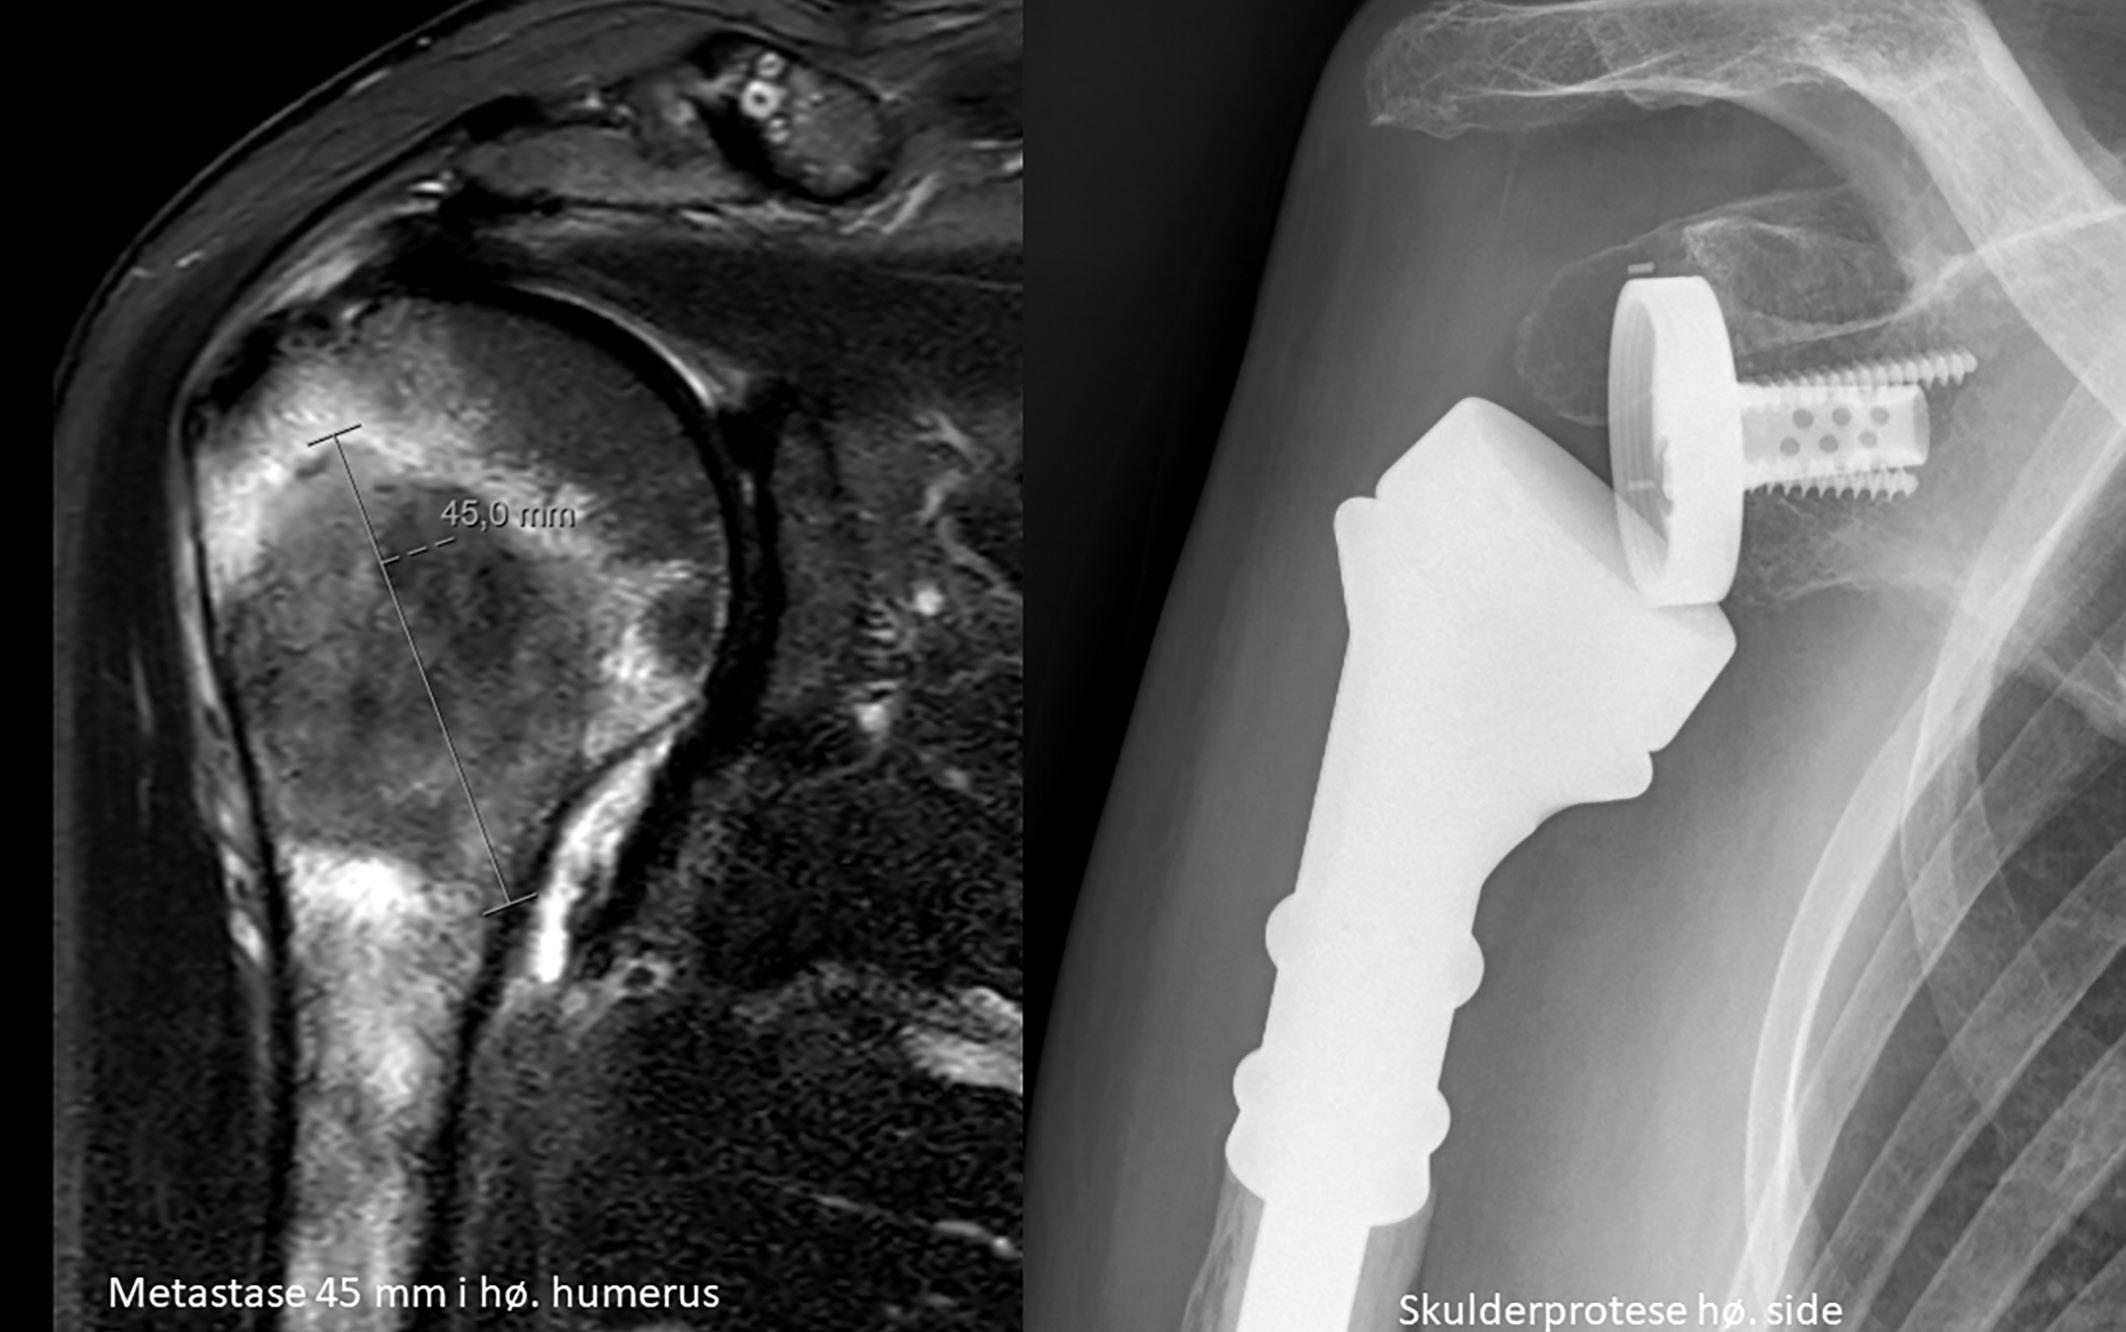

CT thorax/abdomen/bekken 16 måneder etter sykdomsdebut viste ingen tegn til persisterende sykdom. Imidlertid hadde pasienten fått smerter i skulder og 17 måneder etter sykdomsdebut ble det påvist en 4,5 cm stor metas-

2: MR høyre skulder 14 måneder etter sykdomsdebut viste metastase i humerus. Den ble initial strålebehandlet med noe bedring av smertene. Etter hvert tilkom det påny vekst og smerter, og pasienten ble operert med protese etter åtte måneder. Samtykke til publisering av røntgenbilde er innhentet fra pasientens ektemann da pasienten er død.

tase i humerus (Bilde 2). Biopsi bekreftet metastase fra anaplastisk karsinom. NTRAK 1-3 fusjon og RET fusjon/ mutasjon var negative. Pasienten fikk strålebehandling 4 Gy x 7 mot metastase i humerus. Medikasjon ble endret til encorafenib 150 mg og bimetinib 45 mg x 2. Åtte måneder senere ble hun operert med fjerning av tumor i humerus og implantasjon av skulderprotese på grunn av økende vekst og smerter.